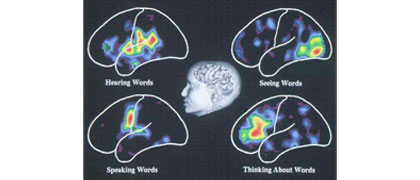

Marcus E. Raichle, Department of Radiology, Washington University, St. Louis, Missouri.